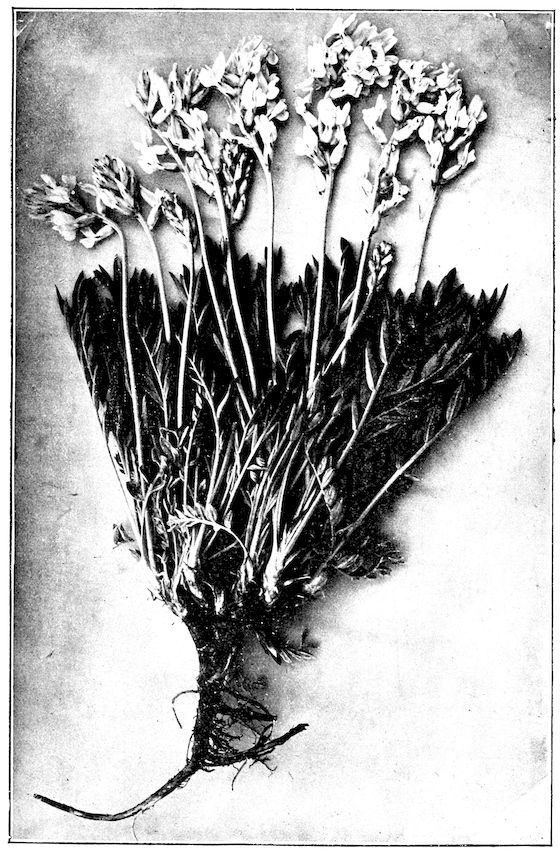

Fig. 1.—Rachitis in a young goat.